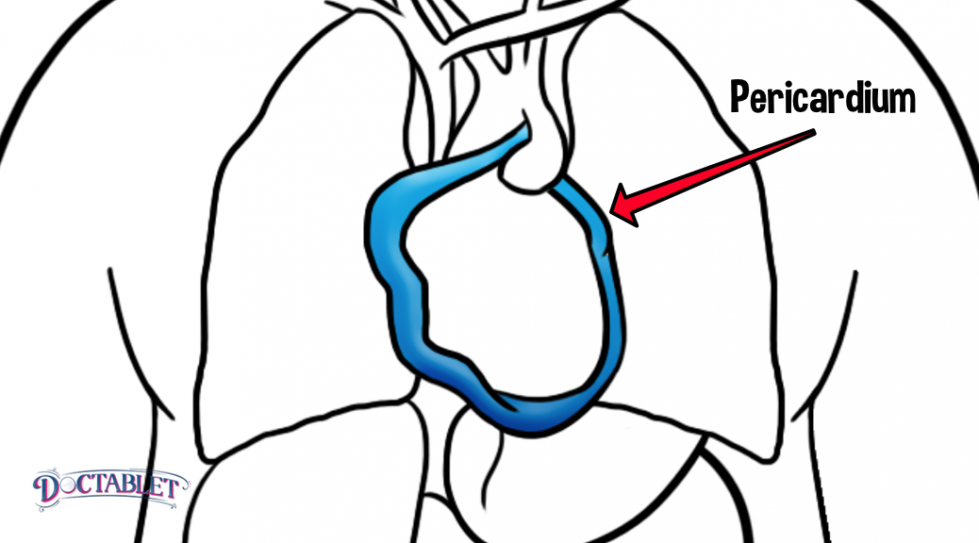

The pericardium is the bag that holds the heart inside. Its made of two bags, one inside the other. The pericardium allows the heart to move freely, shields it from other organs and protects it from infections that can occur in the lungs. The pericardium is made out of a partially elastic tissue that is similar to cartilage, the rubbery material in our joints and knees. There is a very small amount of fluid between the two bags that make up the pericardium. This fluid is there to allow the two bags to slide against one another freely. The pericardium can get inflamed due to a variety of conditions that include viral infections and autoimmune disorders like Lupus and Scleroderma. If it gets inflamed the pericardium can cause chest pain and shortness of breath. An inflamed pericardium can also accumulate fluid between its two bags, a condition called a pericardial effusion.